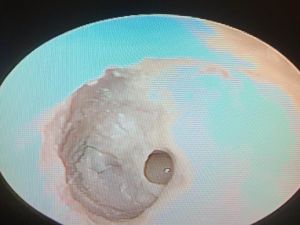

Kulak zarındaki delik, Salihli’de onarıldı